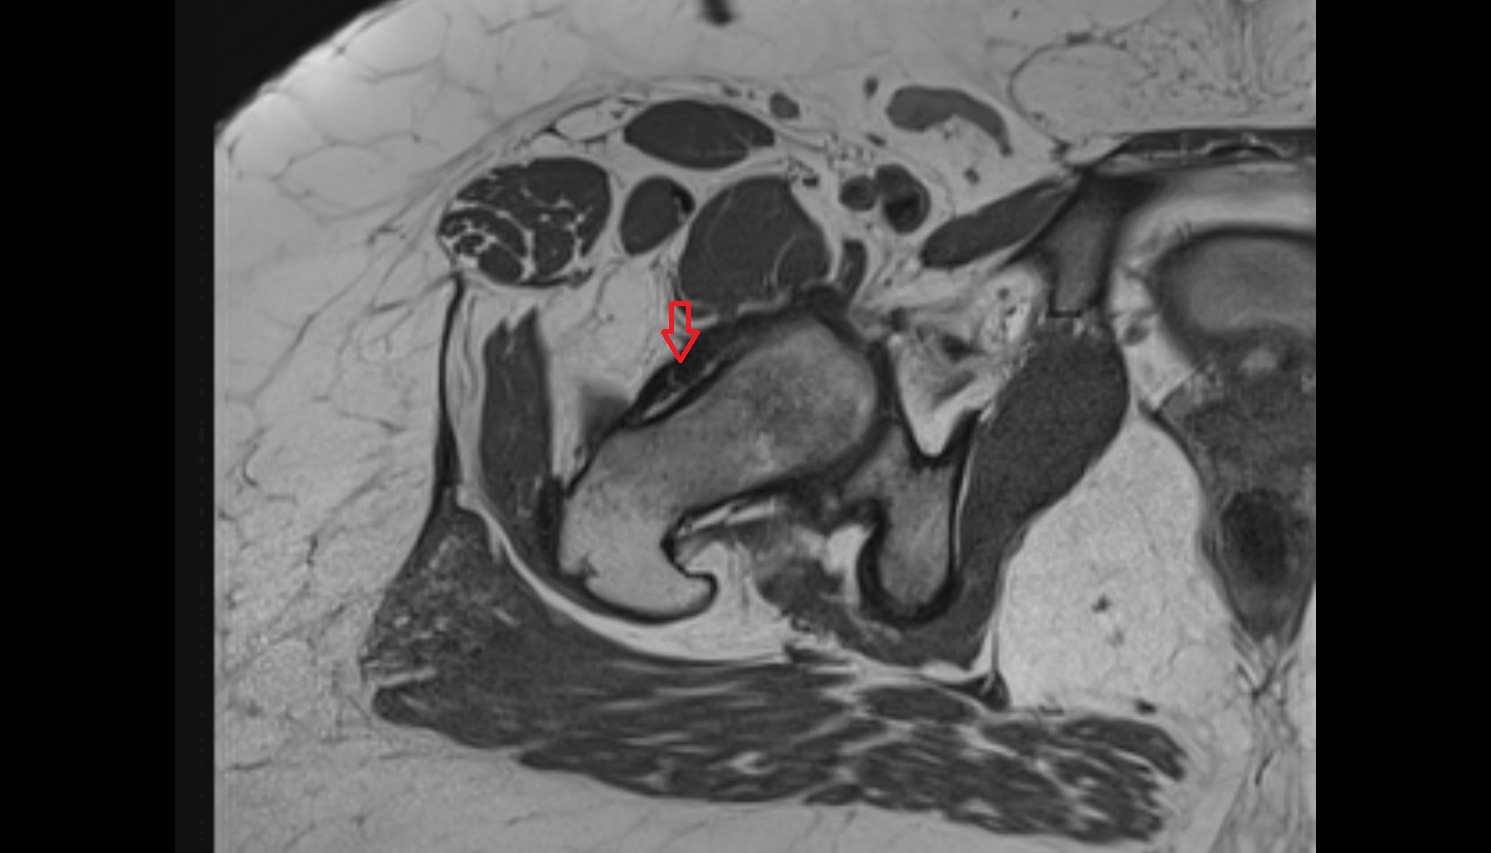

- Placenta

- Uterus (pregnancy)

- Amniotic fluid

- Umbilical cord

- Urinary Bladder in Pregnancy

- Cervix in Pregnancy

- Vagina in Pregnancy

- Fundus of uterus in pregnancy

- Fetal brain

- Fetal hip